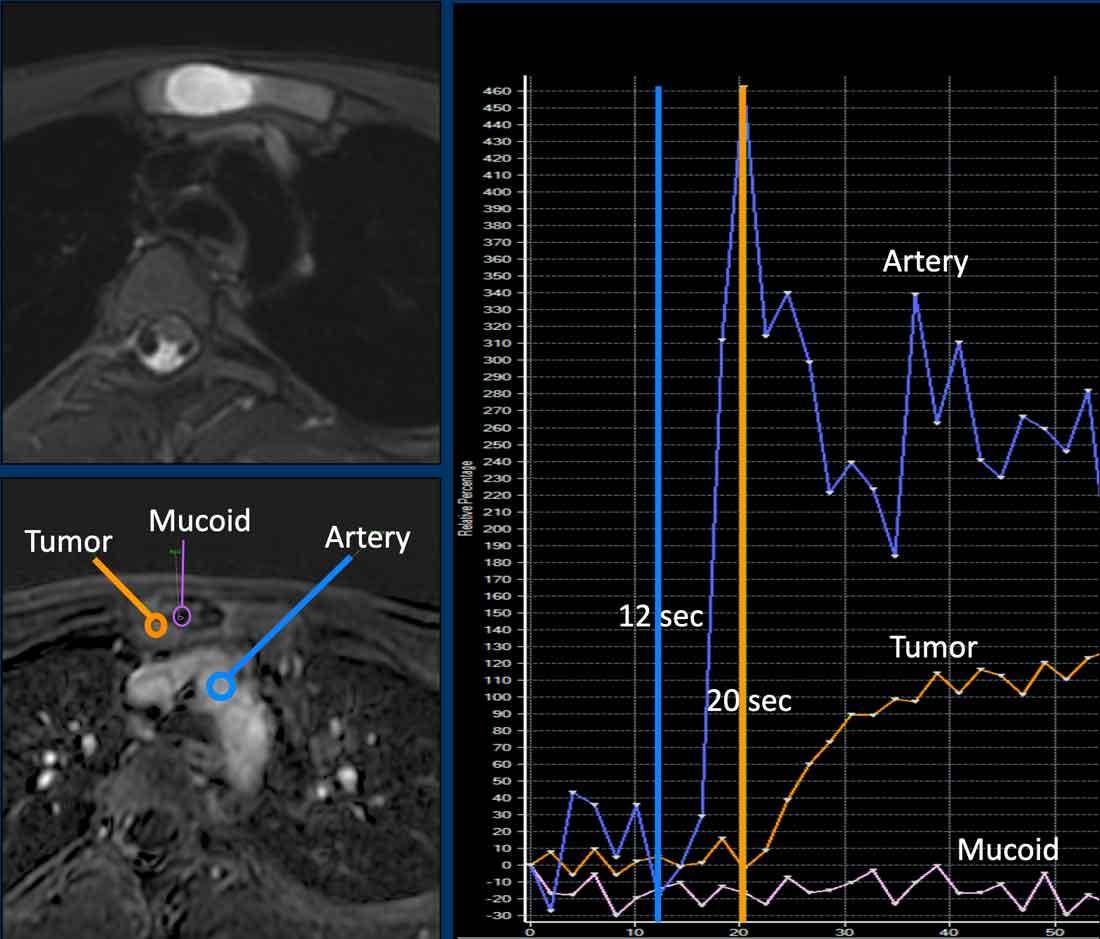

ACT along the posterior cortex in the distal femur showing septonodular enhancement after contrast. Two ROIs were placed, one in the tumor (orange) and one in the popliteal artery (blue).

Ví dụ về một ACT tăng cường chậm (đường màu cam), hơn 10 giây sau động mạch (đường màu xanh lam).